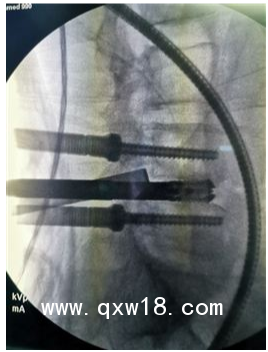

UBE(unilateral biportal endoscopy)技術(shù)是指單邊雙通道內(nèi)鏡下的脊柱手術(shù),是一項(xiàng)新興的微創(chuàng)技術(shù), UBE在脊柱疾病的治療中療效確切,值得進(jìn)一步研究與應(yīng)

UBE的技術(shù)特點(diǎn):

1.兼有內(nèi)鏡放大的視野和開放手術(shù)靈活的操作;

2.應(yīng)用常規(guī)椎間孔鏡器械和脊柱開放手術(shù)器械;

3.對肌肉損傷較小、透視少(可能為零);

4.可以進(jìn)行鏡下融合;

5.對椎管狹窄具有獨(dú)特的優(yōu)勢;

6.有內(nèi)鏡操作經(jīng)驗(yàn)者學(xué)習(xí)曲線較短;

7.條件成熟同樣可以用于頸胸段。

目前UBE手術(shù)適應(yīng)證主要包括:

1.各種類型的腰椎間盤突出癥(側(cè)隱窩);

2.椎管狹窄癥;

3.輕度的腰椎滑脫(BE-TLIF);

4.腰椎不穩(wěn)伴或不伴上述疾病。

UBE技術(shù)較常規(guī)單通道內(nèi)鏡技術(shù)相比,具有其獨(dú)特的優(yōu)點(diǎn):

1.使用關(guān)節(jié)鏡器械及傳統(tǒng)脊柱開放性器械進(jìn)行操作,無需購置特殊孔鏡設(shè)備及器械,高效利用,節(jié)約成本;

2.雙通道設(shè)計(jì),關(guān)節(jié)鏡的獨(dú)特放大功能,手術(shù)視野寬闊清晰,操作通道具有開放性手術(shù)靈活性;

3.使用常規(guī)開放手術(shù)器械進(jìn)行操作,效率更高;

4.對肌肉損傷較小,透視次數(shù)極少(1次即可),減少醫(yī)患X線暴露的風(fēng)險(xiǎn);

5.對椎管狹窄的同側(cè)減壓及對側(cè)減壓具有其獨(dú)特的優(yōu)勢,同時(shí)也可行鏡下融合;

6.同樣適用于一些高齡、需要減壓融合或者翻修等特殊病例的微創(chuàng)處理